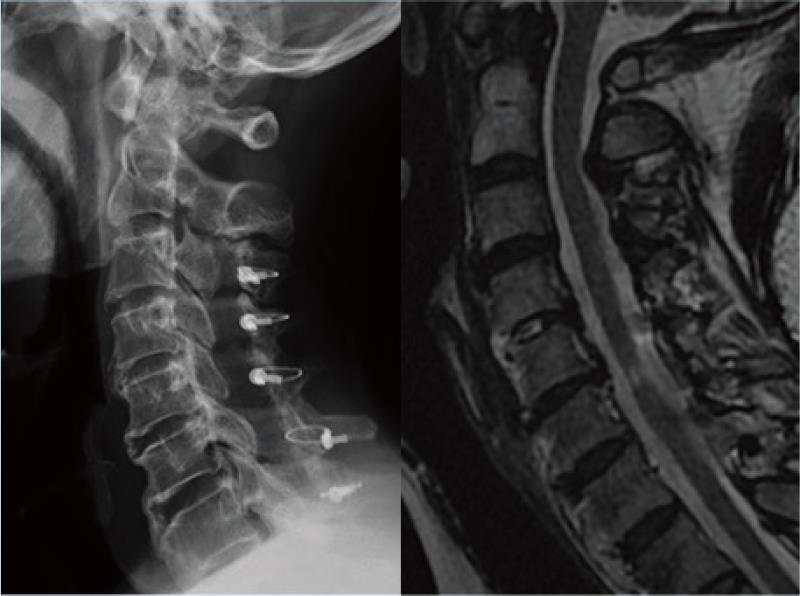

病例3:颈后路保留后方肌肉韧带复合体的单开门椎管扩大成形术

脊髓型颈椎病,术前X线和核磁示多节段椎间盘突出

颈后路保留后方肌肉韧带复合体的单开门椎管扩大成形术,术后随访示椎管扩大良好。